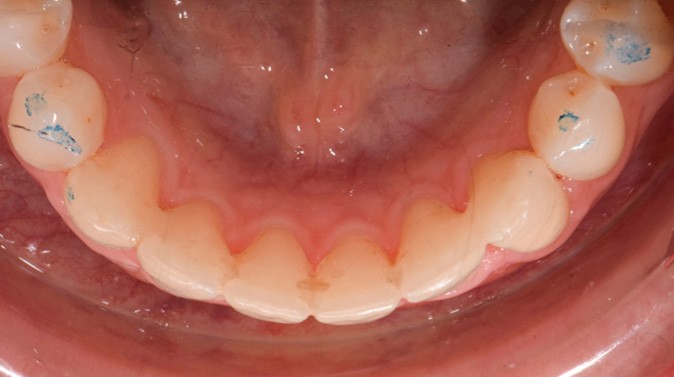

Par exemple, le retraitement d’un patient atteint d’un « Syndrome du fil » [2, 3], au vu de l’état des connaissances imparfaites de l’étiologie de cette situation, méritera une réflexion pour trouver un système de confiance. Une fibre collée est l’une des solutions sécurisantes (fig. 1). Mais, si la langue n’est pas stabilisée au repos comme en fonction, un dispositif amovible type Spring Retainer sera préférable.